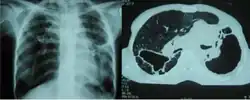

Fibrothorax caused by infection with M lentiflavum. | |